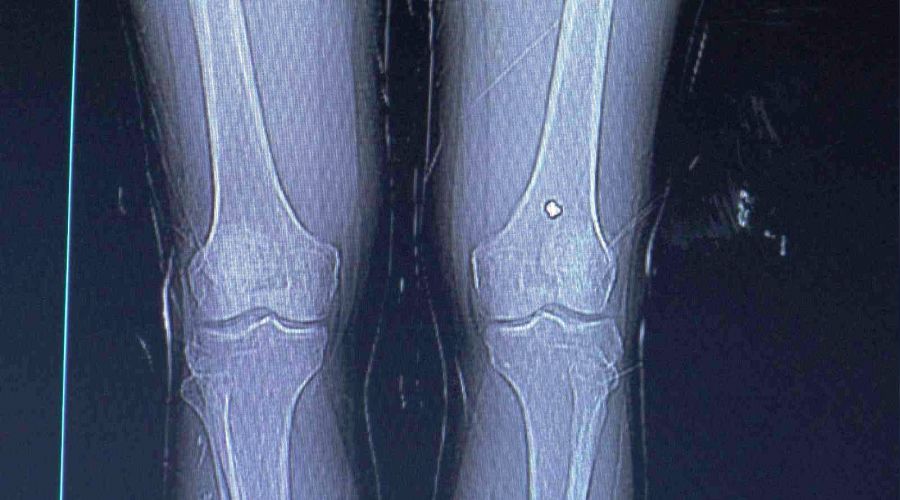

Diz kapağındaki mermi 13 gün sonra fark edildi

Nevşehir'de bacağından tüfekle vurulan şahıs, tedavisinin ardından taburcu edildi. Olaydan 13 gün sonra şikayetleri artınca tekrar hastaneye giden şahsın diz kapağında mermi olduğu anlaşıldı.

13 gün sonra diz kapağındaki ağrıların artmasıyla yeniden hastaneye müracaat eden Değerlier, burada hayatının şokunu yaşadı. Değerlier'in diz kapağında mermi olduğu anlaşıldı. Ortopedi polikliniğine sevk edilen şahsın diz kapağındaki mermi ameliyatla alındı.